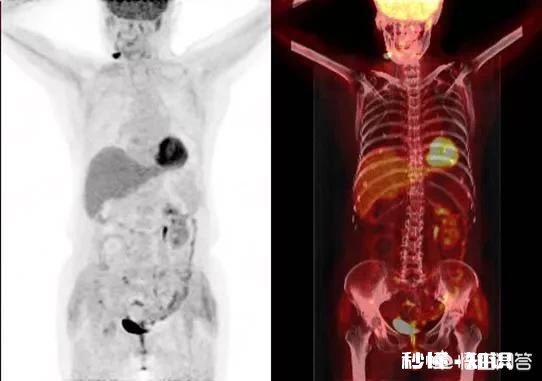

文章插图

像这位胆管细胞癌的病人,73岁时确诊 , 通过胆管引流和放射性粒子植入,已经无症状生存四年,77岁了(本病例来自湘西肿瘤医院文主任) 。